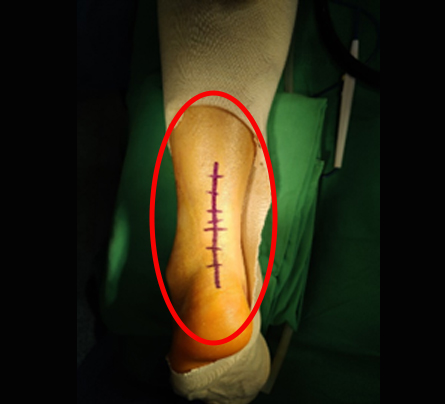

최소침습 재건술

평균 3cm 정도의 최소침습 아킬레스 재건술

특수봉합 테크닉으로 기존의 10cm 이상의

절개창을 획기적으로 줄여서 수술후

통증, 흉터, 감염 위험을 낮추었습니다!